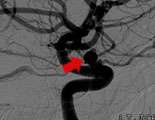

However, many patients receive brain imaging for other reasons, and unruptured aneurysms are discovered. If the anatomy is suitable and if it is felt that the aneurysm does pose a risk for future rupture, the aneurysm can be treated with coil Embolization. Such was the case for this patient, Janet LaRue, who had episodes of confusion that led to an MRI of the brain which disclosed a left carotid-ophthalmic aneurysm. LaRue underwent an angiogram on the left side (Fig. 1) which confirmed the aneurysm.

Fig. 1: a lateral view of the left internal carotid artery before coil embolization.